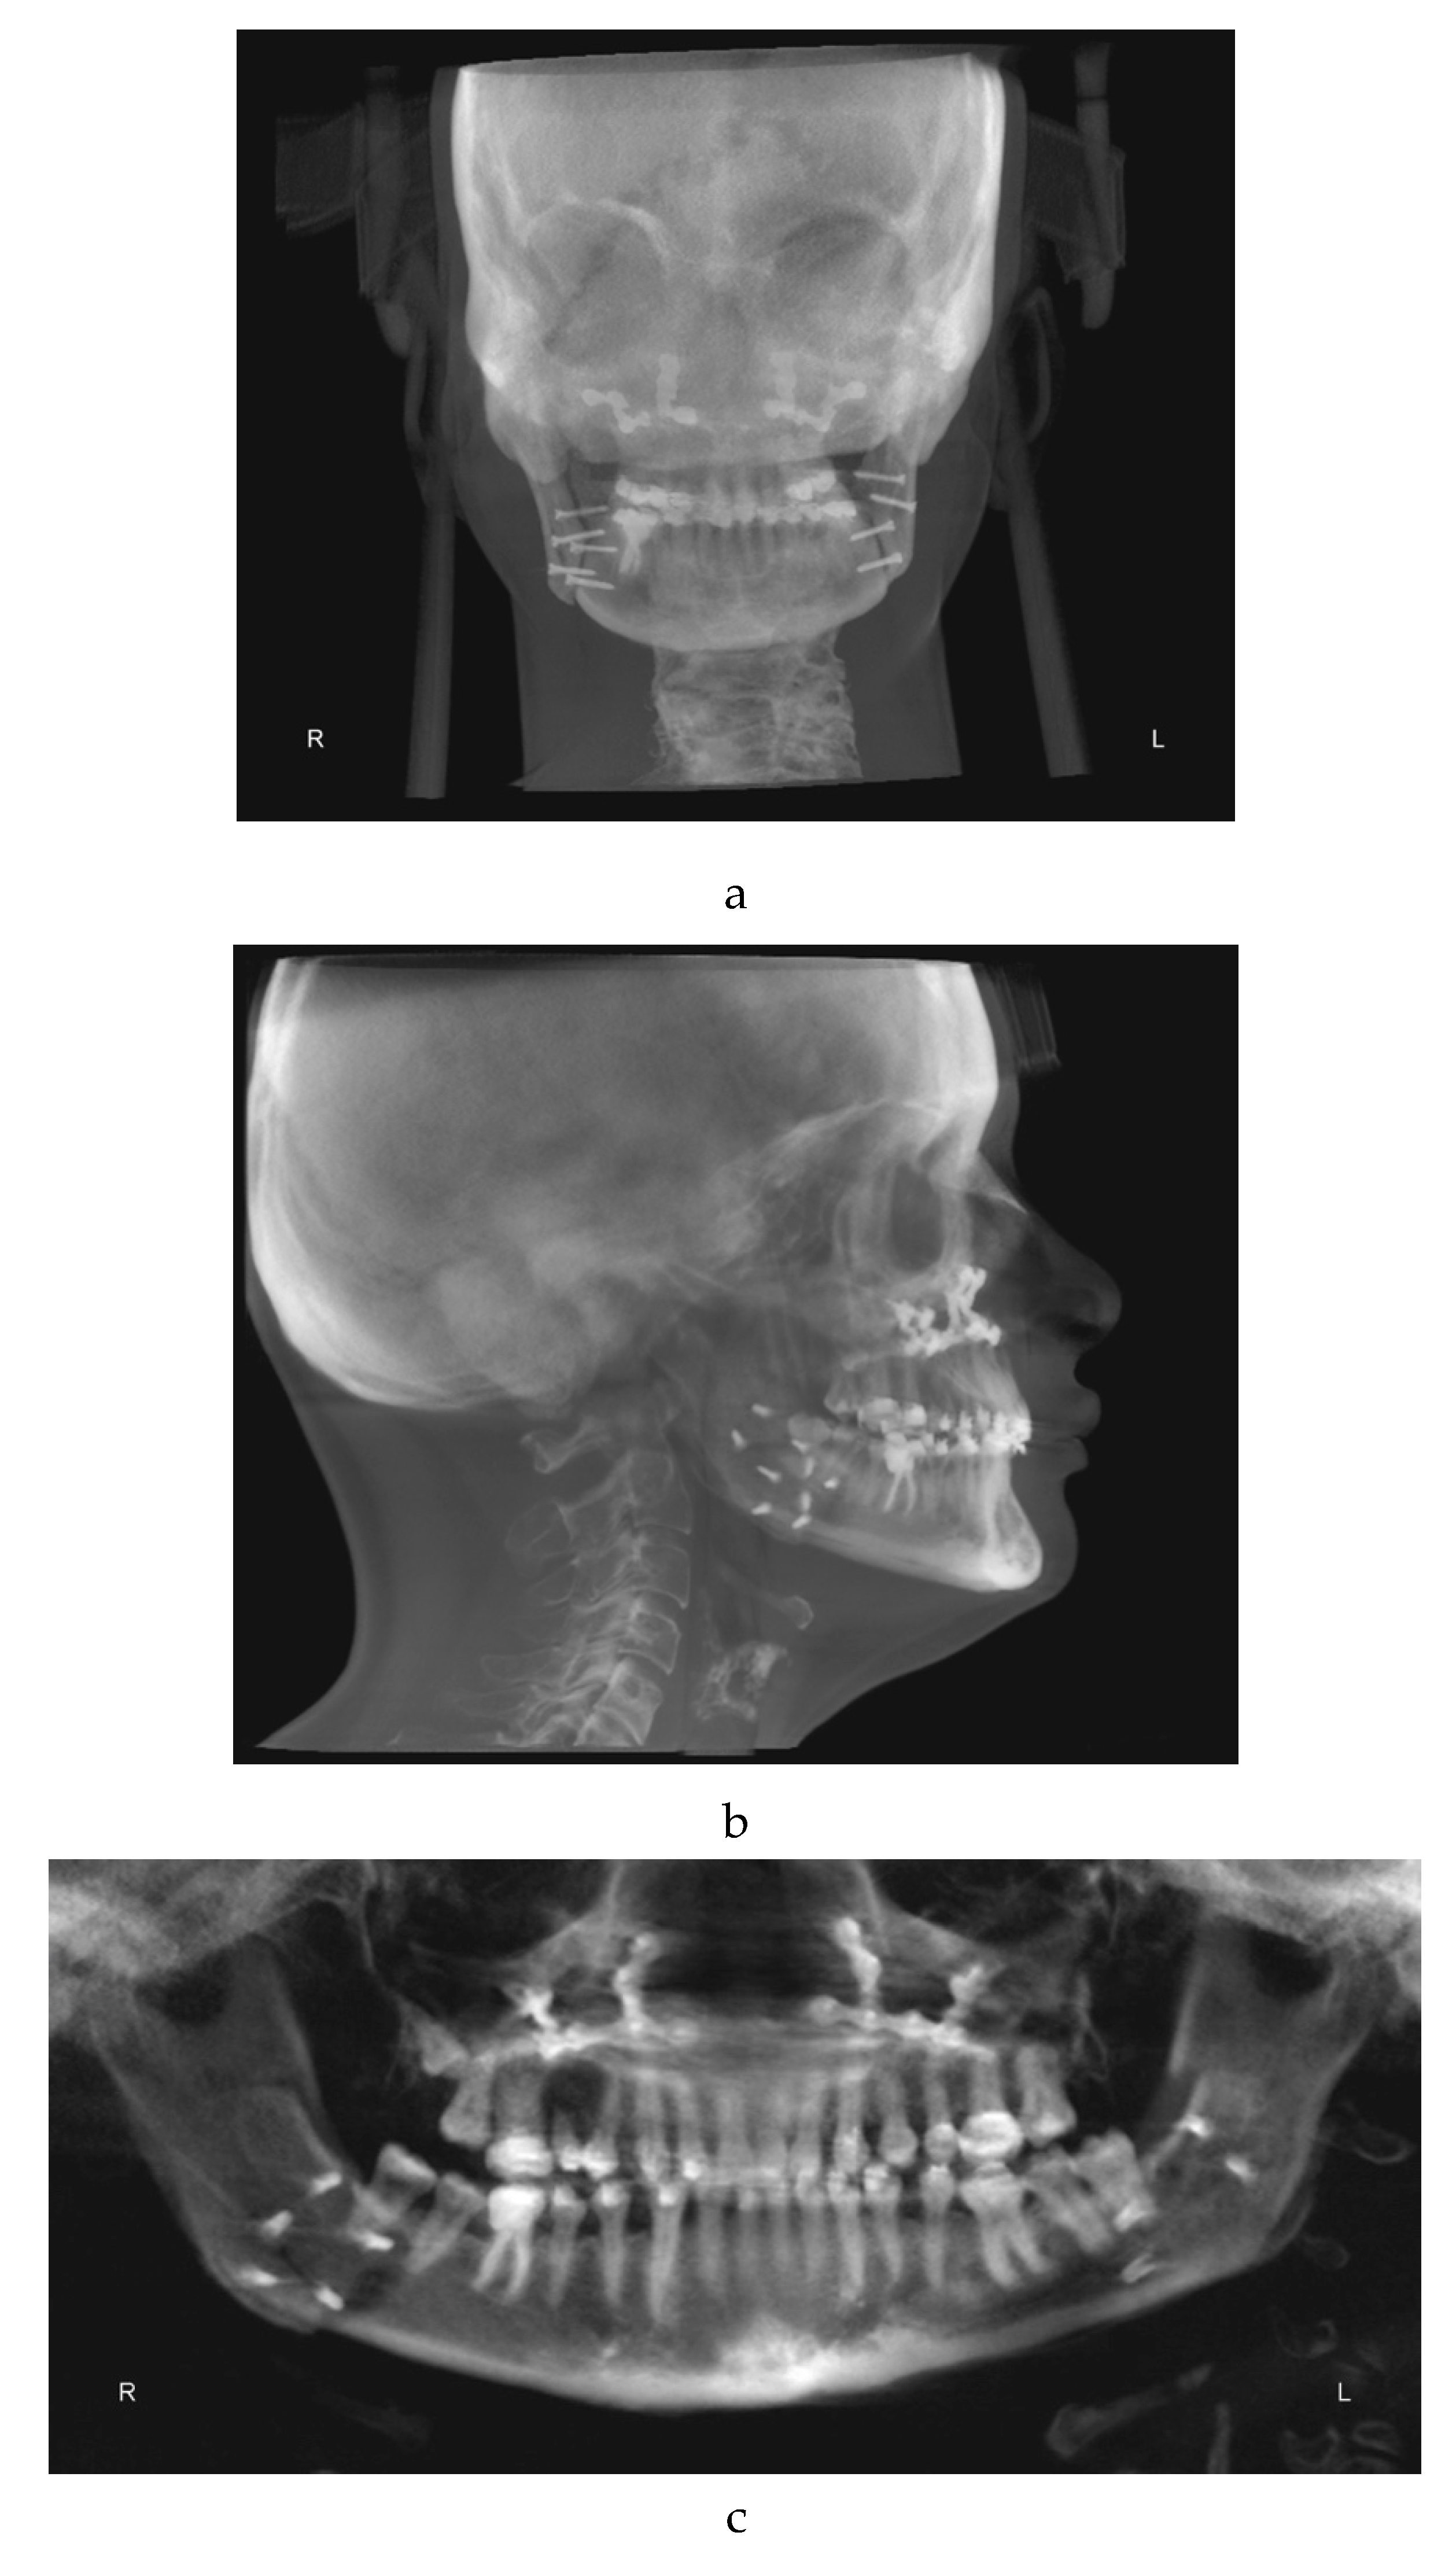

One week later the post-surgical orthodontic treatment phase started (Figure 3a–c).

During the post-surgical orthodontic treatment frequent follow up examinations were performed to reduce the risk of relapse and to complete the alignment. In this phase, element 1.5 was extracted.

It was challenging to regain entirely the patient's collaboration after the surgery because she was scared and demotivated. Her family and therapy team worked for several months to get her to collaborate again. Unfortunately, during this phase a partial orthodontic relapse was recorded. In fact, the patient did not cooperate enough with the intermaxillary maintenance elastic bands. Furthermore, she had to be constantly re-motivated regarding home oral hygiene procedures.

Figure 3. a: antero-posterior projection of the CBCT. b: lateral-lateral projection of the CBCT. c: panoramic projection of the CBCT.